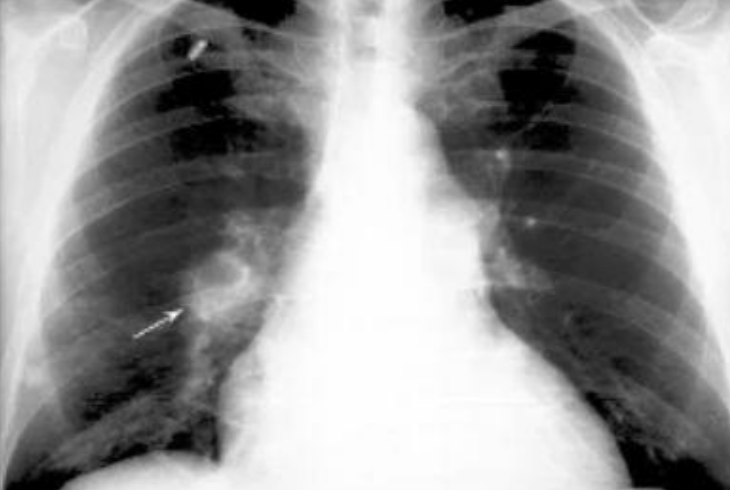

• Joroba de Hampton: atelectasia basal por necrosis del tejido

Joroba de Hampton:

Osificación pleural en domo secundaria a hemorragia e infarto

Joroba de Hampton